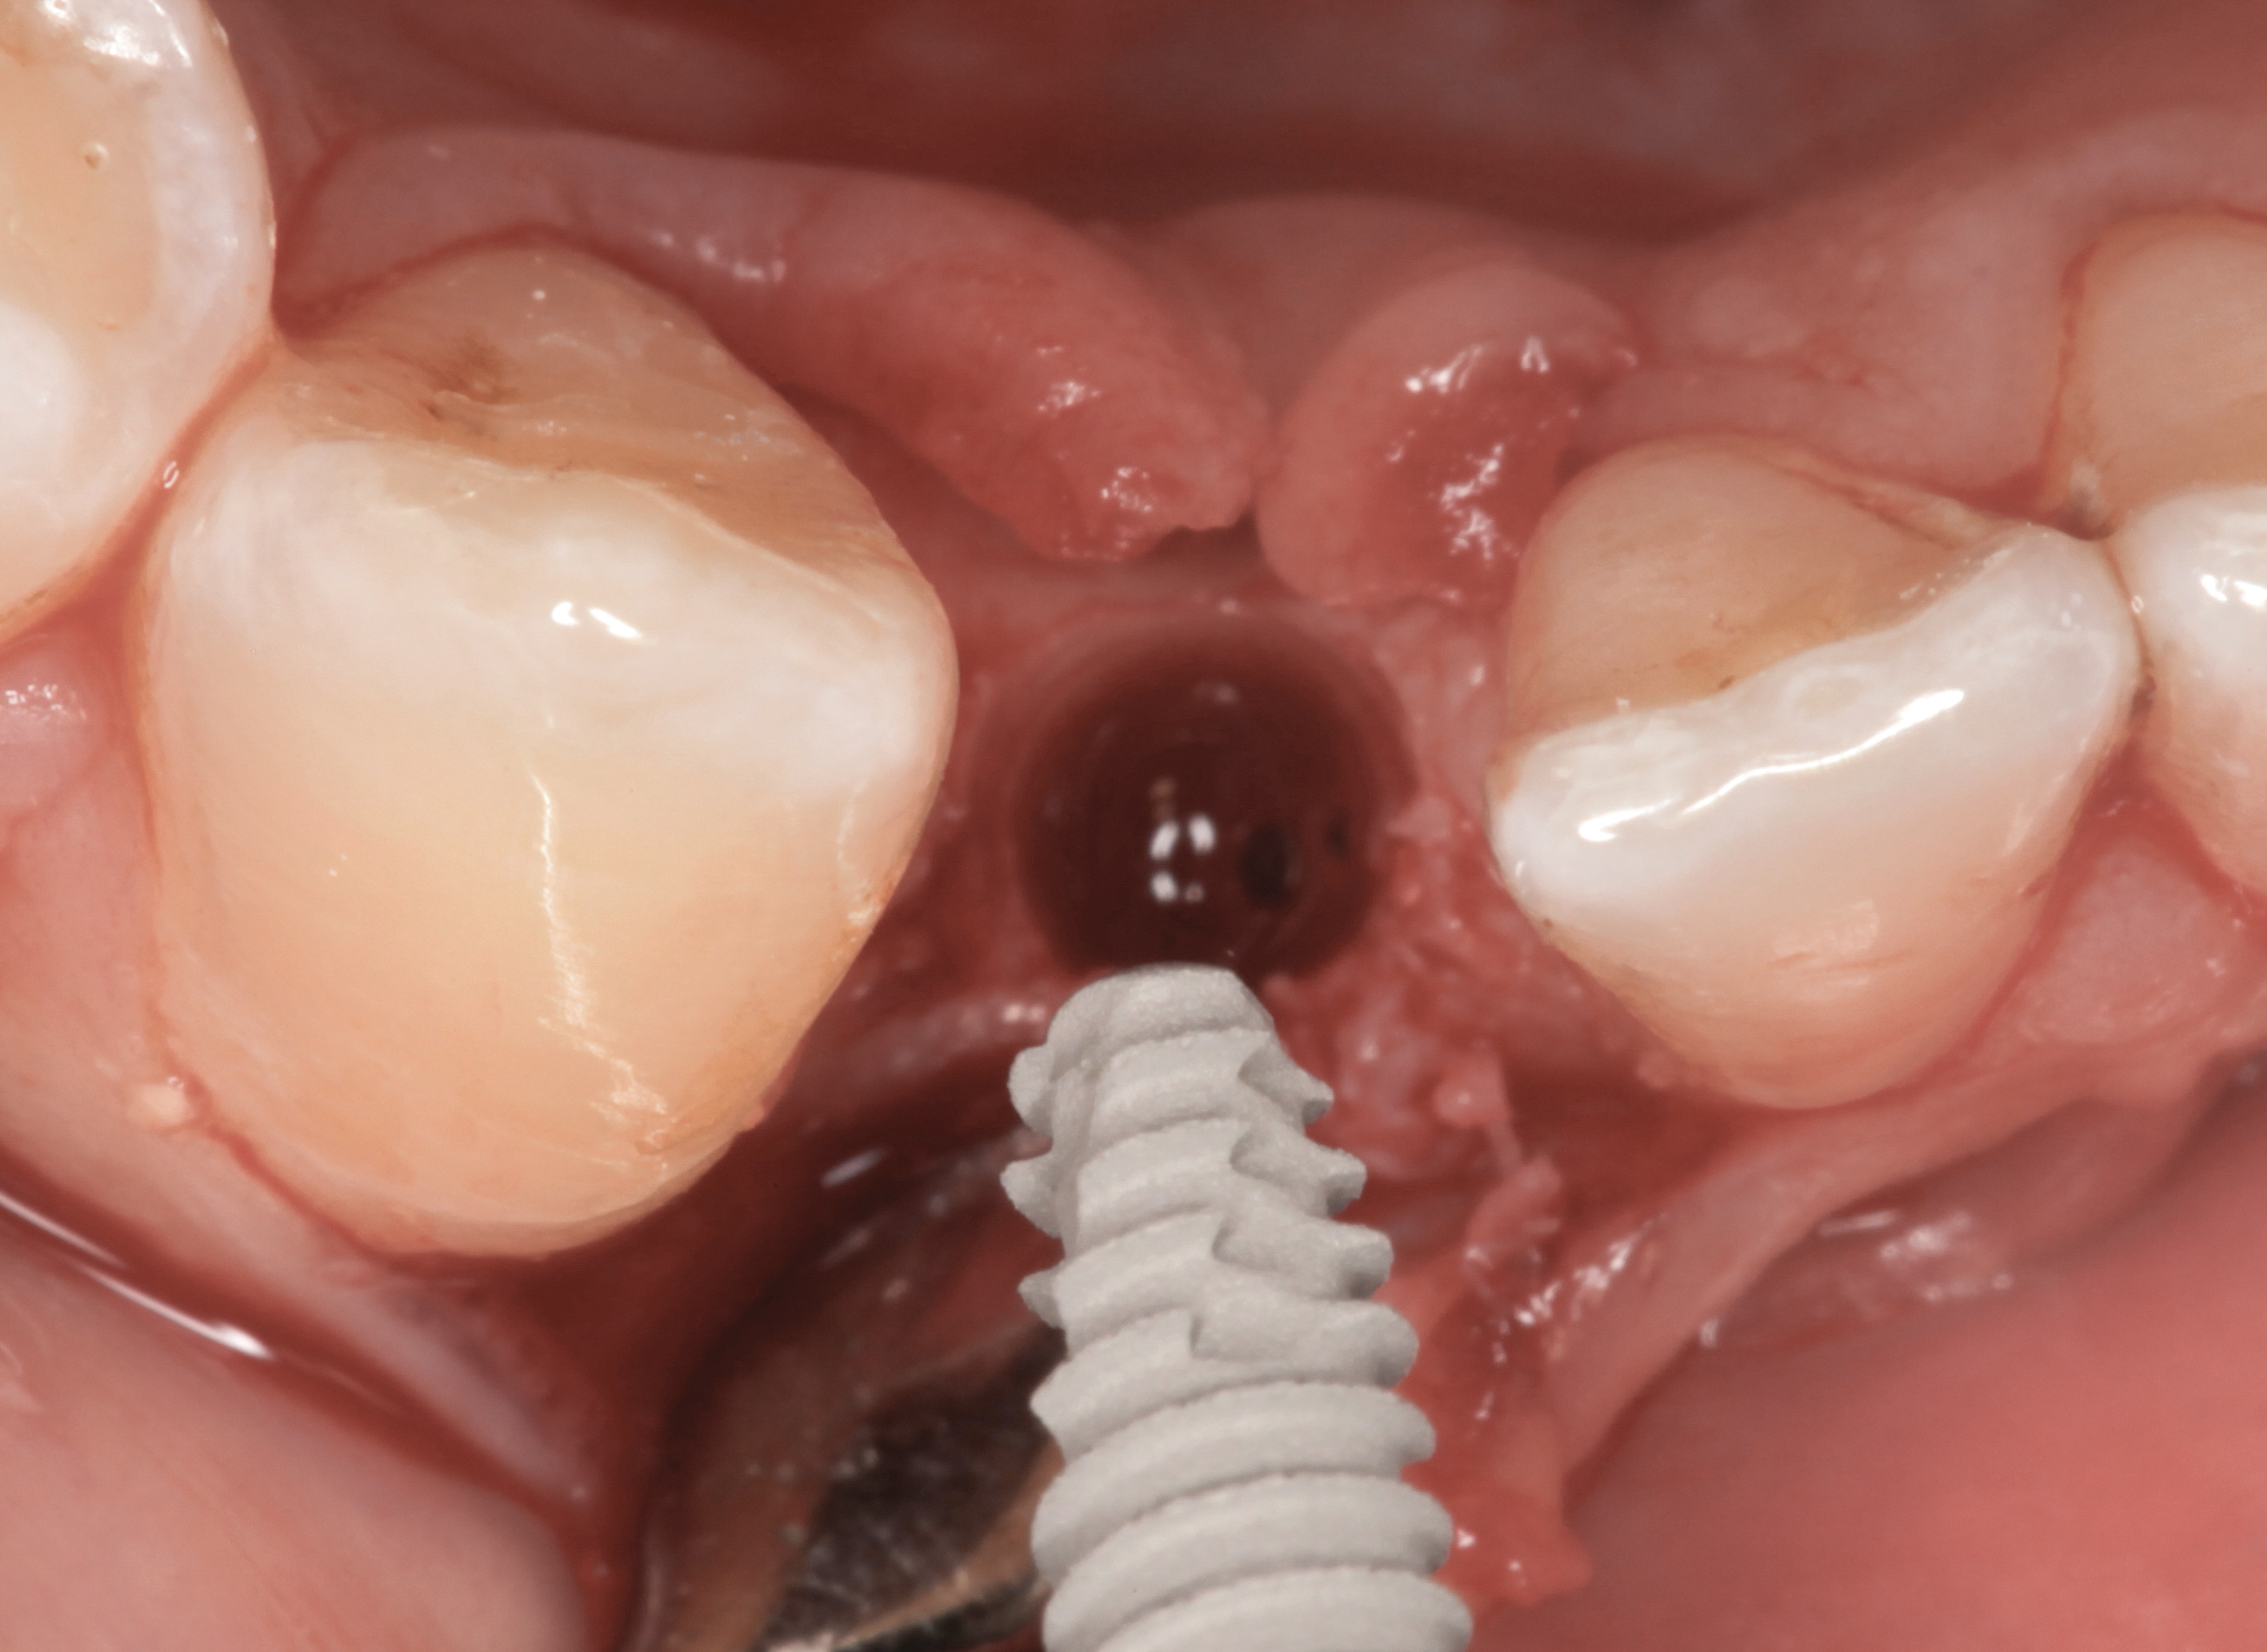

Fig 33. Excessive facial angulation of the implant placement shown with an abutment driver in the access screw hole.

Figure 33

Fig 34. A surgical cover screw was placed in an attempt to decoronate the implant and gain soft-tissue coverage in situ.

Figure 34

The following case report provides an example of this case scenario: A 24-year-old white male presented with congenitally missing tooth No. 26 restored with a single-tooth cement-retained implant restoration. The implant was placed excessively to the facial aspect of the edentulous site and too shallow, and the periodontal phenotype was thin scalloped (Figure 32). In an effort to mimic the lost midfacial soft tissues, pink ceramics were used as a cosmetic facade. Even though the restoration was not in the esthetic zone, the patient was highly displeased with the esthetic outcome and sought remediation.

The crown and screw-retained custom abutment were removed, and a surgical cover screw was placed into the implant, thereby allowing spontaneous gingival augmentation in situ (Figure 33 and Figure 34). Note that the lingual aspect of the implant site was significantly more coronal than the labial aspect, which was positive because the defect would be limited to a facial–lingual defect. A fixed RBR bridge was cemented on the adjacent teeth and used as a tooth-supported transitional provisional restoration (Figure 35). A few weeks were allotted to let the soft tissue heal and migrate around the cover screw (Figure 36) to see if there would be complete coverage, thereby allowing a soft-tissue augmentation procedure to be performed with primary flap closure as in clinical scenario No. 2. The major obstacle in achieving a positive tissue response was that the implant depth was also deficient because the implant–abutment connection was at the level of the free gingival margin. It was decided that the best treatment option would be to remove the implant. A high-powered reverse-torque device (Fixture Remover Kit, NeoBiotech, www.neobiotechus.com) was used to remove the implant atraumatically (Figure 38 through Figure 41). The implant socket was allowed to heal for several months not unlike an extracted tooth (Figure 42). A new implant was placed in a better position from both a restorative and esthetic perspective (Figure 43), and after a few months of healing, a new crown was made (Figure 44). A satisfactory functional and esthetic result was achieved (Figure 45 and Figure 46) without employing pink porcelain.